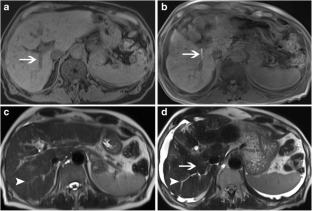

Fig. 3